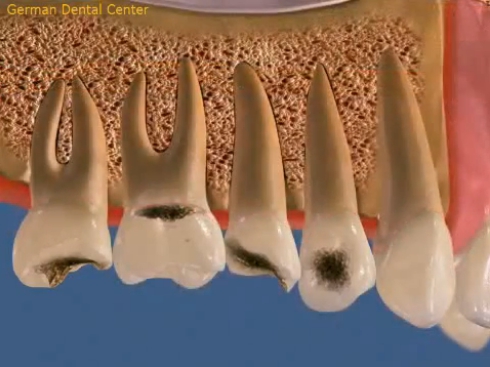

- Терапевтическая стоматология